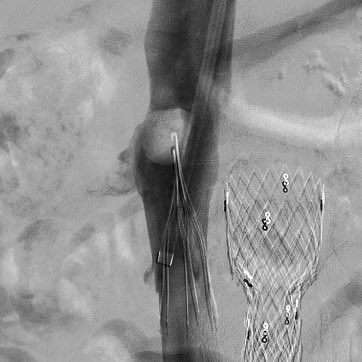

This #IVCfilter was placed after a #trauma in a patient with DVT. During removal, the apex was imbedded and removed with standard equipment using the “hangman” aka “loop sling” technique of flossing a glide wire through the apex #iRad